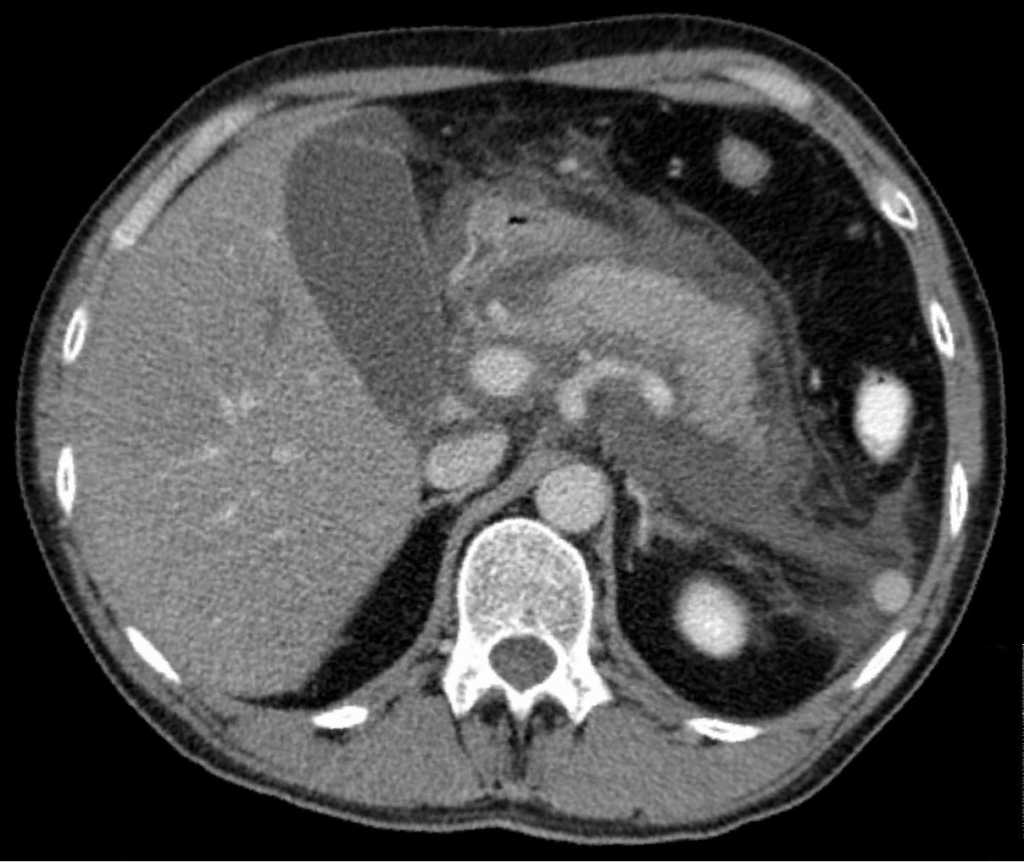

췌장염의 CT 소견 (출처 : 위키미디어)

영상 의학 검사는 매우 유용한 검사입니다. 일반적으로 복부 CT(전산화 단층촬영)를 우선 시행합니다. 실제로 췌장염이 있는지, 있다면 어느 정도 단계인지, 합병증이 동반되어 있는지를 알 수 있습니다. 이외에 MRI(자기공명 영상), 복부초음파, 자기공명 이자 조영술(MRCP), 초음파 내시경(EUS), 내시경 역행 췌담관 조영술(ERCP) 등의 검사도 할 수 있습니다.